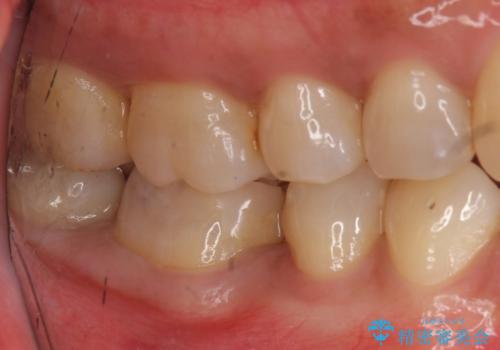

写真・レントゲン画像からもわかる通り、適合の良いクラウンを入れることができました。